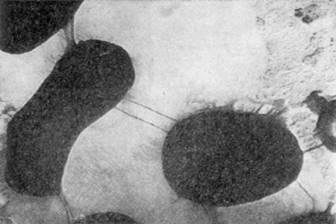

Все микобактерии неподвижны, окрашиваются по Граму положительно. На ранней стадии развития (впервые сутки) микобактерий имеют палочковидное строение клеток, и в этот момент они морфологически похожи на проактиномицетов, находящихся во второй стадии развития. Палочковидные клетки микобактерий, в отличие от бактериальных, имеют неправильные очертания: контуры их искривлены, в разных местах они неодинаковой толщины, часто колбовидно раздутые, клетки более или менее изогнуты, одиночные или соединены в пары или короткие цепочки (рис 2.1).

Рис.2.1 Клетки Mycobacterium

Цепочки никогда не бывают правильно очерченными и прямыми, строго расположенными в одну линию, как это наблюдается в культурах бактерий; обычно они угловато искривленные. На рисунке 2.2 показан общий вид односуточных культур разных видов микобактерий, наиболее типичных по своему строению и расположению клеток. Величина клеток микобактерий меняется в зависимости от вида культуры и состава среды. В молодом возрасте чаще всего клетки имеют длину 2,5 - 7,0 мкм [5].

Рис.2.2 Общая картина микроскопических препаратов микобактерий. Односуточные культуры на синтетической агаризованной среде.

В микрокультурах, развивающихся в жидких питательных cредах, микобактерии человеческого и бычьего видов образуют косы, жгуты, завитки, скопления. Микрокультуры легко обнаруживают при обычной микроскопии мазков, окрашенных по методу Циля-Нильсена. В препаратах, приготовленных из первичных посевов, при исследовании под фазовым контрастом обычно различают гомогенные зернистые элементы, среди которых встречаются сферические светопреломляющие структуры.

В культурах, выделенных от крупного рогатого скота, чаще находят шаровидные образования правильной формы, одинаковых размеров, а также отдельно лежащие нитевидные структуры [3].